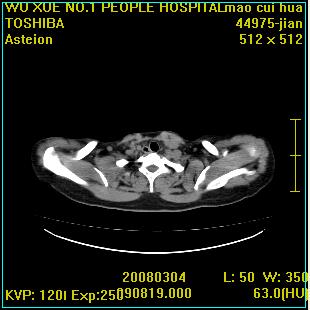

标题: CT12025:男,50岁,左肩活动受限半年。 [打印本页]

标题: CT12025:男,50岁,左肩活动受限半年。

肩关节骨质破坏呈小囊状,其周软组织轻度肿胀,余未见异常。

考虑:肩袖损伤。建议mri。

左侧肱骨头密度不均匀,高低混杂,周围软组织略肿胀,考虑结核性病变。

左侧肱骨头密度不均匀,高低混杂,髓腔密度稍高,周围软组织略肿胀,肌间隙模糊,考虑慢性骨髓炎可能。密切结合临床!